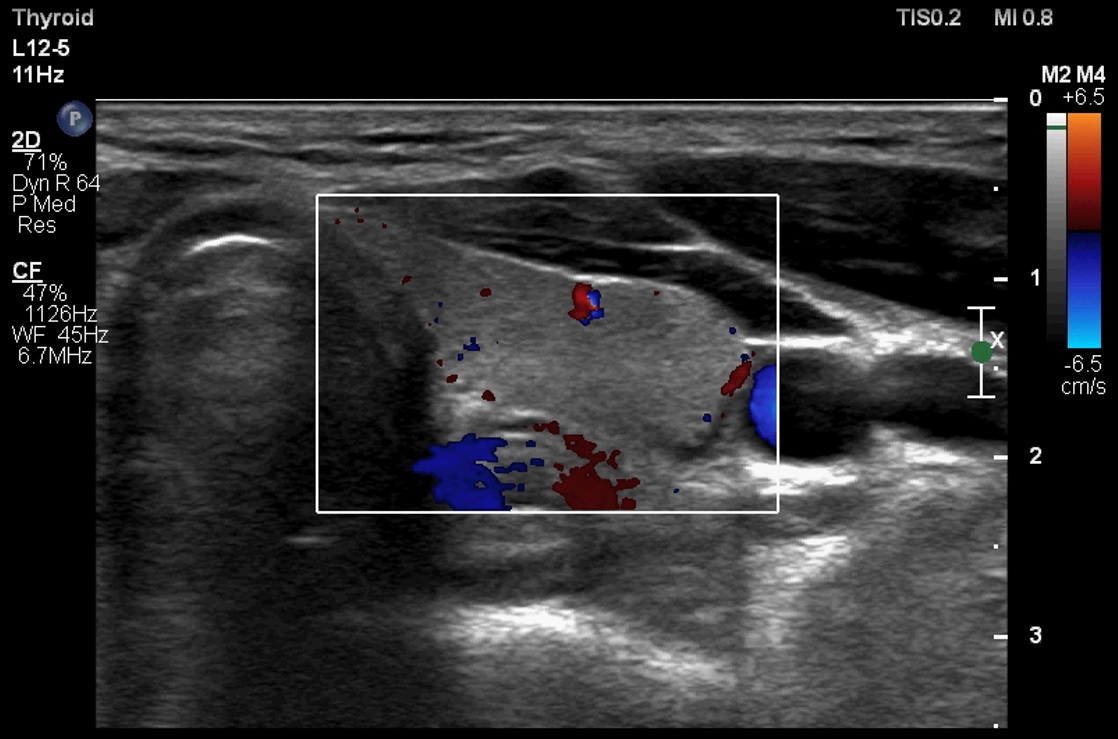

ابعاد و حجم تیروئید در سه قسمت لوب چپ (تصویر 1)، ایسم (تصویر 2) و لوب راست (تصویر 3) بررسی و معاینه میشود. همچنین سونوگرافی داپلر نیز در دو قسمت چپ (تصویر 4) و راست (تصویر 5) انجام میشود. لازم به ذکر است، همانطور که در قسمت آزمایشگاه توضیح داده شده است، هورمون TSH3 نیز به منظور غربالگری اختلالات کمکاری (کمتر از 0.01 µIU/mL) و پرکاری (بیشتر از 4 µIU/mL) انداز گیری و گزارش میشود. |